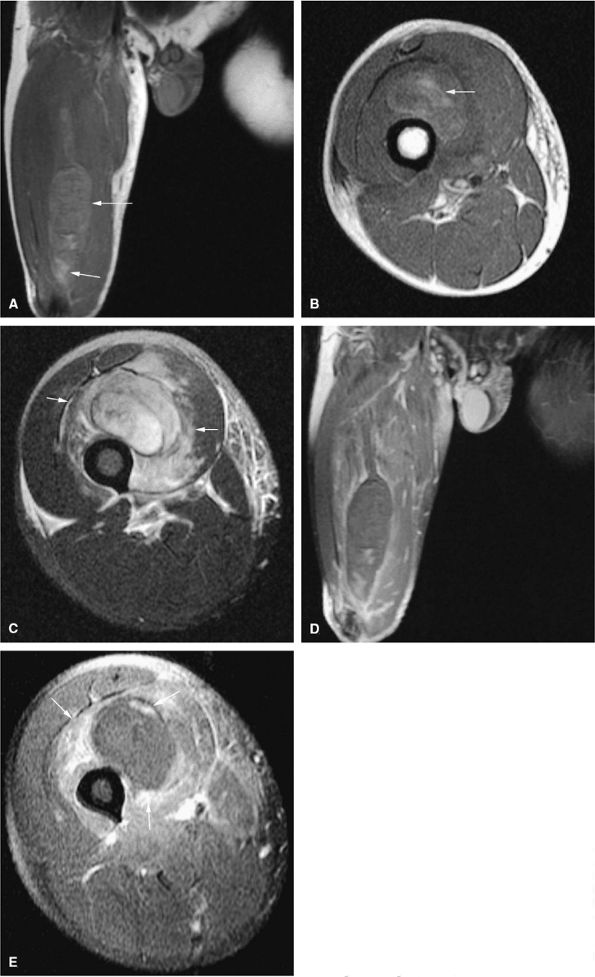

FIGURE 14-73 ● Parosteal osteosarcoma. Anterior coronal (A) and axial (B) T1-weighted images show a large lobulated mass of low signal intensity arising from the metadiaphyseal surface of the tibia (arrows). Tumor is hyperintense on sagittal (C) and axial (D) fat-suppressed T2-weighted fast spin-echo images. Tumor enhancement is noted on axial fat-suppressed T1-weighted image (E) following administration of intravenous gadolinium.